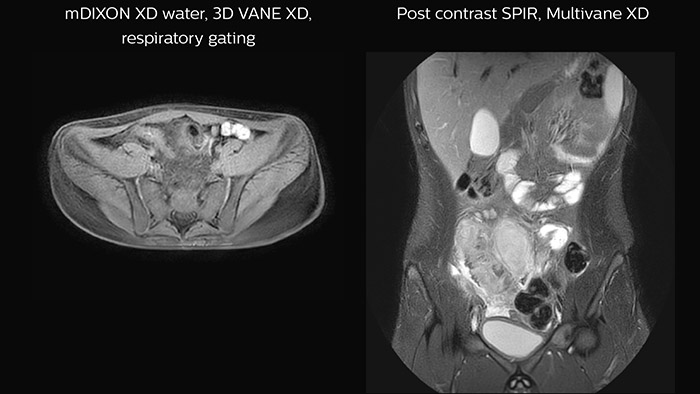

• Using latest techniques such as 3D VANE XD for free-breathing abdominal imaging, MultiVane XD for motion-free imaging in short scan time, mDIXON for excellent fat-free imaging.

Neuro-oncology ExamCards for 3.0T

Body-oncology ExamCards for 1.5T

Examples of 3.0T neuro-oncology ExamCards (left) and 1.5T body-oncology ExamCards (right) for a selected age group. The list of sequences from the highlighted ExamCard is shown on the right. These ExamCards are part of the Philips DACH Pediatric Reference Scan Protocols